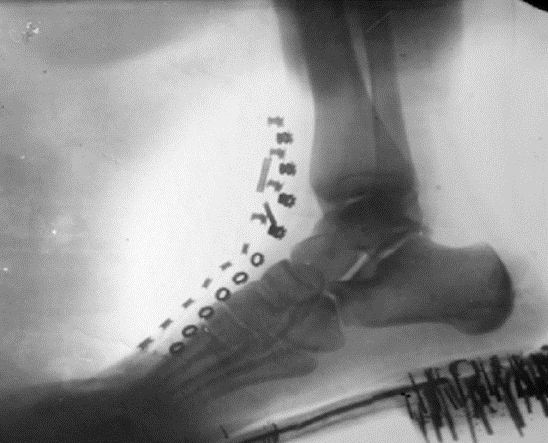

5.  1920s-1970s, people used to x-ray their feet to see if a new shoe fit well, especially popular for children’s shoes! There was little to no knowledge of x-ray shielding prevention, and everyone nearby would be exposed, not just the user’s foot!